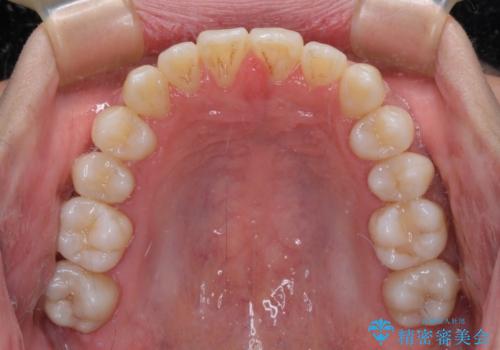

- 前歯のクロスバイトを気にして来院された患者様です。

1年半後に結婚式が控えているとのことで、ワイヤー矯正で早めに治療を終えることを希望されました。

骨格的に下顎が前方に位置していましたが、歯列矯正で改善できると判断し、ワイヤー装置にて矯正治療を行うこととしました。

骨格的な左右差も顕著であったため、正中は合わず、上下前歯の一部が接触しない咬み合わせとなることが予想されましたが、正中はもともとのズレが小さかったことから、合わせることができました。

治療期間も10か月間という短期間で終了し、患者様には大変満足していただきました。